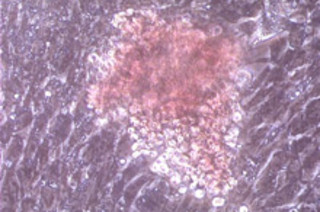

Image: Luigi Adamo and Guillermo Garcia-Cardena. A blood cell colony emerges in response to blood flow.

The two studies, published in Nature and Cell, examined the phenomenon in mice and zebrafish, respectively. In the mouse study, the research teamplaced mouse embryonic stem cells in a centrifuge-like device that mimics sheer stress — the frictional force blood creates when it flows over cells — in a mouse’s aorta. In early embryos, blood stem cells first form on the floor of the aorta. Later in development, they migrate to the bone marrow. Embryonic stem cells exposed to the same magnitude of sheer stress as found in the mouse aorta produced hematopoietic stem cells [Science News]. Different magnitudes of stess, like the amount of force found in a human aorta, showed no such result. Zon’s team found similar results in the zebrafish study, and also showed that a mutant type of embryo that never develops a heart beat, known as a “silent heart” embryo, had fewer blood stem cells.